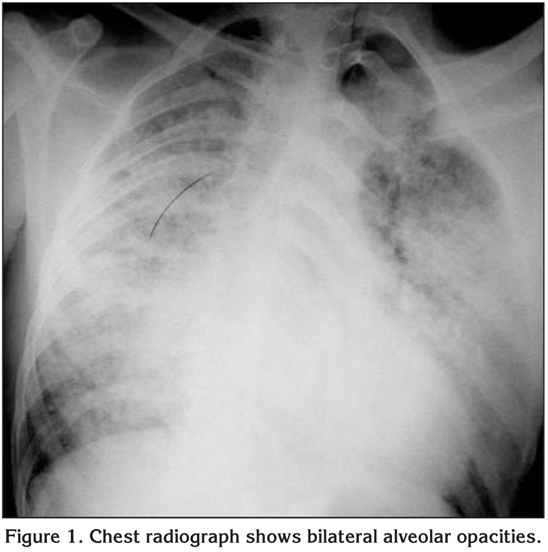

A 23-year old man was admitted to our respiratory intensive care unit with short of breath, cyanosis and agitation which was developed acutely after varicocele operation under epidural anesthesia lasted for one hour. Bupivacain, fentanyl, remifentadyl and midazolam were used for epidural anesthesia. There was no blood transfusions history of patient. On admission his temperature was 38?C, heart rate 117 was beats/minute, respiratory rate was 48 breaths/minute and blood pressure was 110/70 mmHg. He was tachypneic, agitated and cyanotic. Bilateral ralles were heart during auscultation and tachycardia was present. The rest of the physical examination was unremarkable. His blood count and biochemical analysis were normal. Oxygen saturation was 81% while breathing oxygen at FiO2 of 0.5. Arterial blood gas analysis showed hypoxemia with respiratory alkalosis with a PaO2/FiO2 score of 100. A chest radiograph demonstrated bilateral alveolar opacities consistent with ARDS (Figure 1). An electrocardiogram showed sinus tachycardia. Bedside echocardiography was performed which revealed no evidence of global hypokinesia, all the chambers were normal, left ventricular ejection fraction was 65%. The right atrium and right ventricle were normal with minimal tricuspid regurgitation. A diagnosis of ARDS was made and the patient was initiated on NIMV (BiPAP, Respironics, Inc, Murrysville, PA, ABD) with an expiratory/inspiratory positive airway pressure of 4/10 cmH2O with a FiO2 of 0.5. Over the next hour, there was partially improvement in oxygen saturation, respiratory rate and arterial blood gas parameters. PaO2/FiO2 score was calculated 116. He was continued with an expiratory/inspiratory positive airway pressure of 5/12 cmH2O with a FiO2 of 0.7. After 48 hours of continuous ventilation (with short breaks for daily activities), there was a significant improvement in the PaO2/FiO2 score and radiographic findings (Figure 2). PaO2/FiO2 score was calculated 213. He was gradually weaned off the NIMV and discharged after a total hospital stay of four days. Nonspecific antibiotic was continued for four days. At a one-week follow up, he was asymptomatic and his chest radiography was normal.

Figure 1